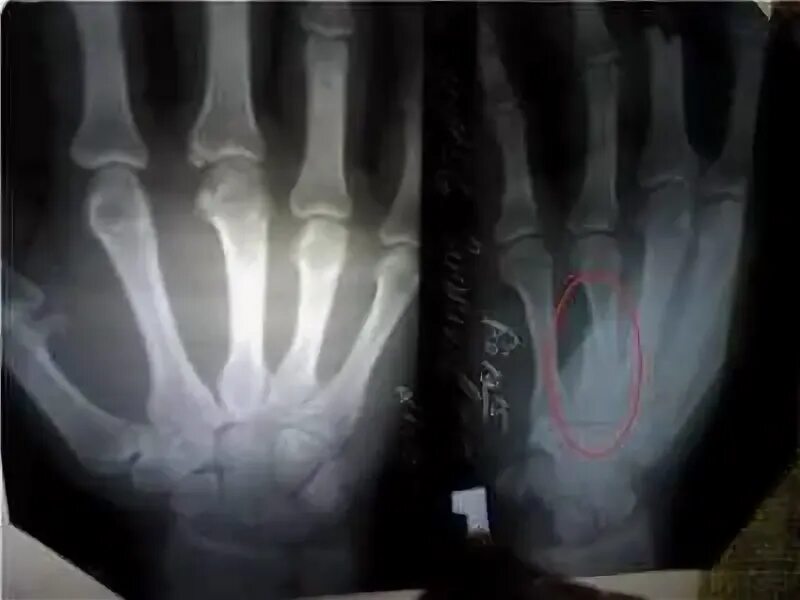

Почему не срастается